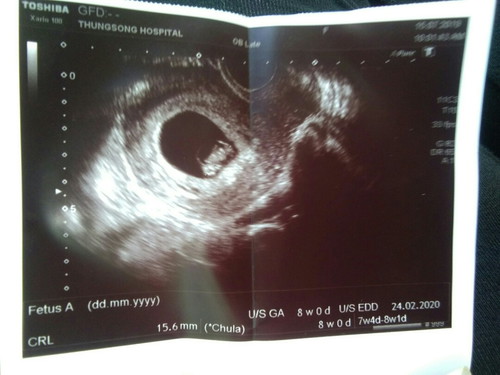

เมื่อวันจันทร์ไปตรวจอันตราซาวคะ8week คุณหมอบอกว่าฝากครรภ์ได้เลย แล้วเอาบัตรมายื่นพยายาล พยาบาลยอกว่ามีสิทธ์ของบัตร 30 บาท ต้องฝากที่อนามัยอย่างเดียว ไม่สามารถฝากโรงพยาบาลได้ อันนี้จิงป่าวค่ะ?? แต่พอถามคนอื่นเค้าก็มีสิทธ์30. แล้วทำไมเค้าฝากได้ อีกอย่างเราก็เสี่ยงหลายอย่าง ฝากอนามัยไม่มีเรื่องมืออะไร กังวลมากคะ